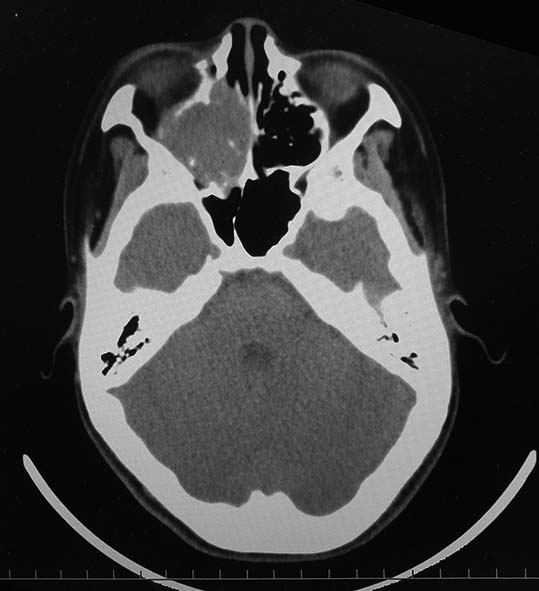

CT所見

CT画像および肺腫瘤生検組織